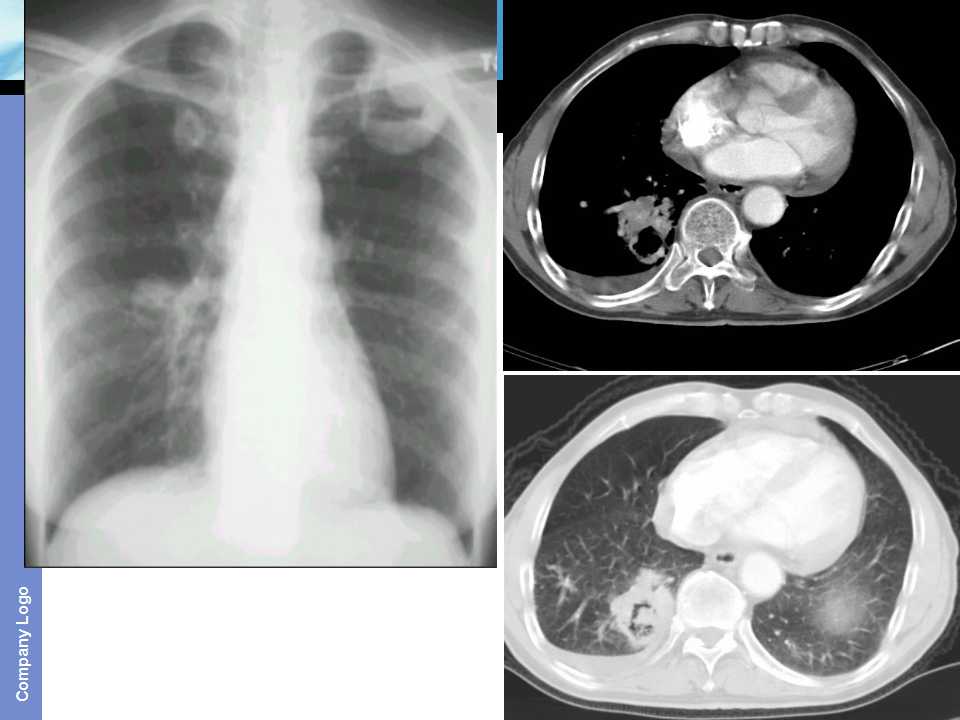

肺癌影像诊断